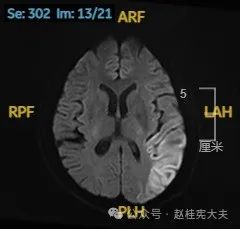

入院后给予精氨酸,左卡尼丁,辅酶Q10,维生素E等治疗。患者病情稳定好转中,2天后意识清楚,语言表达仍欠佳。当天复查颅脑磁共振如下:

以上为患者发病后3次的颅脑磁共振片子,临床诊断基本上可以确认了,希望患者逐渐恢复!